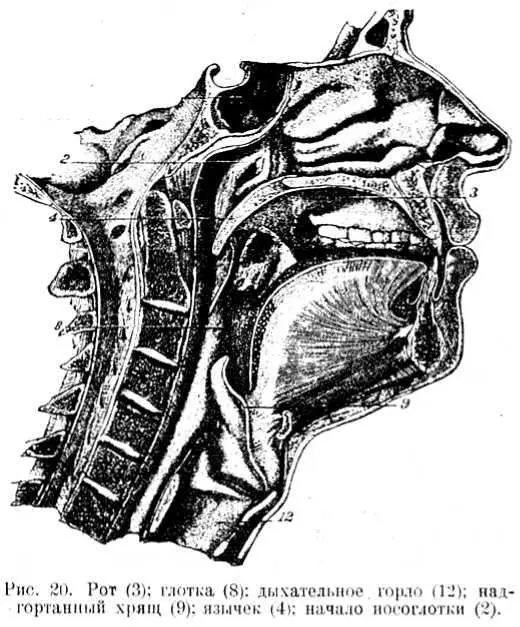

Наши путешественники снова прошли через правое предсердие, а дальше через правый желудочек в легкие; оттуда они снова попали в левое предсердие, а потом в левый желудочек. Теперь они из левого желудочка двинулись не вниз, а вверх, в рот. (Рис. 20).